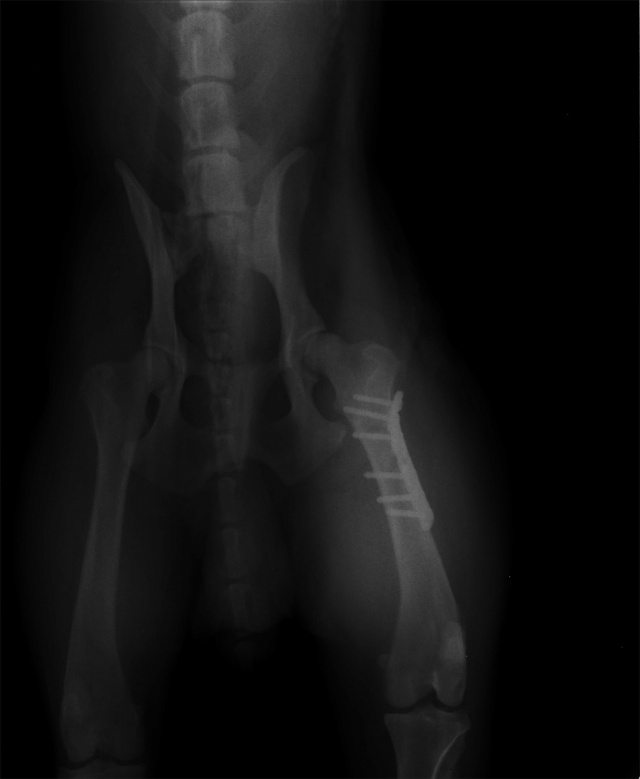

Tehtud ortopeediline op Hoiuaiga Kliinikus. Kõik on korras. Käpp pareneb!

Tagumise käpa luumurd.